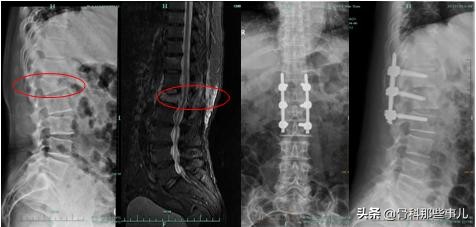

椎体骨折,骨折块向后错位造成神经压迫;核磁共振看到水肿带一直延伸到后柱,微创手术不合适